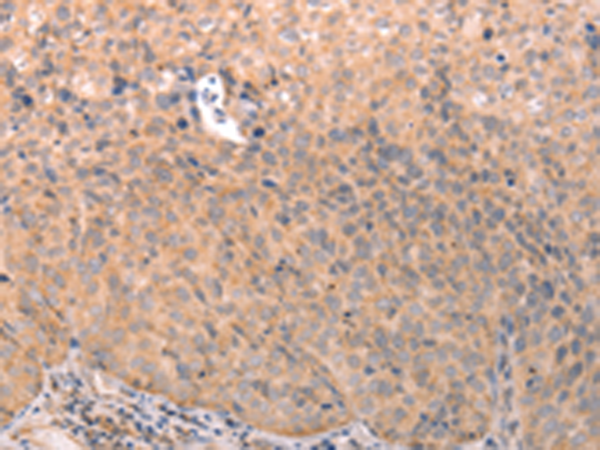

ELISA, IHC |

IHC positive control: |

Human cervical cancer and human thyroid cancer |

IHC Recommend dilution: |

25-100 |